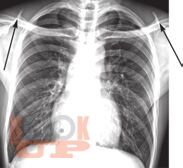

В настоящей монографии подробно описаны и проиллюстрированы изменения легких, сердца и костной системы при различных патологических состояниях в пульмонологии, кардиологии и ревматологии. Сопоставлены клиническая и рентгенологическая картины при различный нозологических формах проявления многих заболеваний. Все представленные результаты рентгенологических исследований верифицированы и подтверждены клинически. Монография предназначена для врачей-рентгенологов, пульмонологов, кардиологов и ревматологов, а так же врачей других специальностей, занимающихся диагностикой и лечением органов грудной клетки.